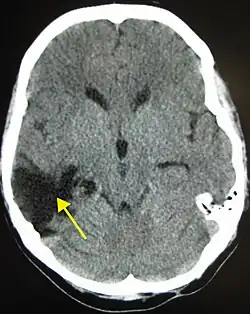

Los hematomas epidurales son los que se localizan entre la lámina interna craneal y la duramadre. Como se ha mencionado están asociados con fracturas de cráneo y ruptura de la arteria meníngea media o sus ramas. Son más comunes en las regiones parietales y temporales y son raros en las regiones frontales y occipitales. Se encuentran entre el 8% y 10% en pacientes con TCE grave. En la TAC, se ven como lesiones hiperdensas y biconvexas y debido a que no existe un espacio entre la duramadre y el hueso no suelen propagarse a menos que superen la adherencia de la duramadre. Estos hematomas son raros en infantes debido a que el cráneo es deformable lo que les confiere una protección. Además son raros en adultos mayores de 60 años debido a la adherencia débil de la duramadre al cráneo.[15]

Los hematomas subdurales se encuentran entre la cara interna de la duramadre y la superficie cerebral. Se encuentra entre el 20% y el 25% en pacientes con TCE grave. Son el resultado de hemorragia en las venas anastomóticas de la corteza cerebral superficial o ruptura de los senos venosos o sus tributarios y se asocian con daño en el tejido cerebral subyacente. Más específicamente se ha demostrado que un buen número de estos hematomas se deben a la ruptura de venas puente parasagitales.[31][32] Normalmente se expanden en la mayor parte de la convexidad cerebral pero no pueden propagarse al hemisferio contrario debido a la existencia de la hoz del cerebro. Los hematomas subdurales se clasifican en agudos, subagudos o crónicos dependiendo de la aparición y duración de estos y su aspecto característico en la TC:[15]

Los hematomas intraparenquimales se encuentran inmersos en la sustancia cerebral y tienden a ocurrir en TCE graves con preferencia sobre los lóbulos frontales y temporales. Estos hematomas se asocian con contusiones del tejido cerebral aledaño. Las hemorragias subaracnoideas son comunes después de un TCE grave y no producen efecto de masa o hematoma y pueden estar asociadas con vasoespasmo postraumático.[15] Un caso especial de hemorragias es la hemorragia de Duret, que tiene lugar en la protuberancia o el mesencéfalo y se asocia con hernia uncal.[15]

Contusiones

Las contusiones se encuentran en 20% al 25% de los pacientes con TCE grave. Son lesiones heterogéneas compuestas de zonas de hemorragia puntiforme, edema y necrosis que aparecen en las imágenes de TC como áreas de hiperdensidad puntiforme (hemorragias), con hipodensidad circundante (edema), suelen estar localizadas en la cara inferior del lóbulo frontal y la cara anterior del lóbulo temporal por su relación con el ala mayor del esfenoides. También se pueden encontrar en la superficie de impacto y en la superficie contraria a este, el llamado efecto golpe-contragolpe. Cuando estas evolucionan se parecen más a los hematomas intracerebrales y su ubicación depende el posible efecto de masa.